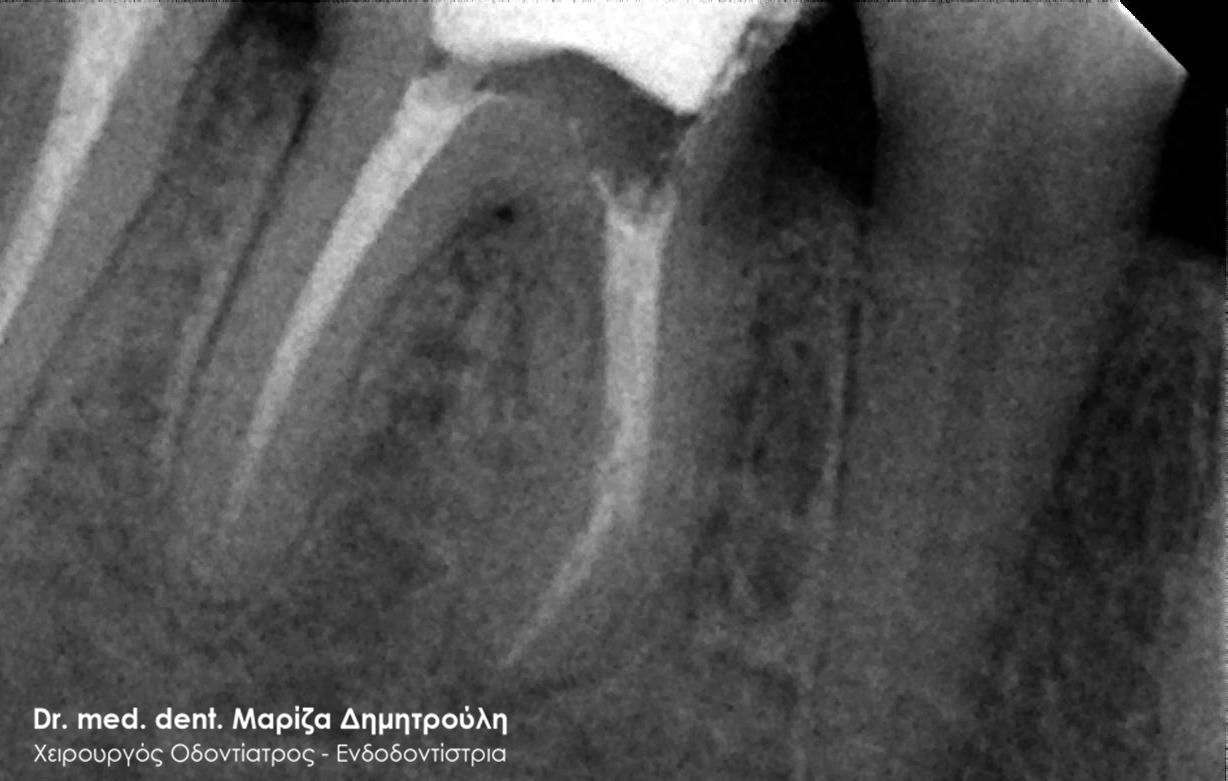

Η ασθενής προσήλθε με έντονο πόνο στο ιατρείο και είχε λάβει τις προηγούμενες μέρες αντιβίωση, εφόσον στην άνω αριστερή πλευρά της είχε οίδημα. Μετά την κλινική εξέταση διαπιστώθηκε η ύπαρξη ενός συριγγίου υπερώια μεταξύ των δύο άνω αριστερών γομφίων. Πραγματοποιήθηκε ακτινογραφία με την τοποθέτηση ενός κώνου γουταπέρκας για τη διάγνωση του υπαίτιου δοντιού, που είχε προκαλέσει την εμφάνιση του συριγγίου. Σύμφωνα με όσα αποκάλυψαν η κλινική και ακτινογραφική εξέταση ακολούθησε η έναρξη απονεύρωσης στο δεύτερο άνω αριστερό γομφίο, δεδομένου οτι είχε ένα βαθύ λευκό σφράγισμα ρητίνης που εκτεινόταν στο ύψος του νεύρου του δοντιού. Το δόντι είχε έντονα συμπτώματα πόνου κατά την επίκρουσή του.

Μετά την ολοκλήρωση της απονεύρωσης στο δεύτερο άνω αριστερό γομφίο το δόντι είναι ασυμπτωματικό. Η αποκατάσταση του δοντιού πραγματοποιήθηκε με λευκό σφράγισμα ρητίνης, εφόσον το έλλειμμα των οδοντικών ιστών ήταν μικρό και δε χρειαζόταν η προστασία του δοντιού με θήκη / στεφάνη δοντιού.

Σε δεύτερη φάση θα ακολουθήσει η επανάληψη απονεύρωσης στον πρώτο άνω αριστερό γομφίο, καθώς η απονεύρωση του δεν καλύπτει όλο το μήκος των ριζών του δοντιού και το δόντι μετά το πέρας της ενδοδοντικής θεραπείας συνεχίζει να πονά.

ΠΡΙΝ

ΜΕΤΑ

Εικόνα του δοντιού μετά τη διάνοιξή του και την επεξεργασία των ριζικών σωλήνων του δοντιού

Κλινική εικόνα του δοντιού με το υλικό έμφραξης στους ριζικούς σωλήνες του

Αποκατάσταση του δοντιού με λευκό σφράγισμα ρητίνης